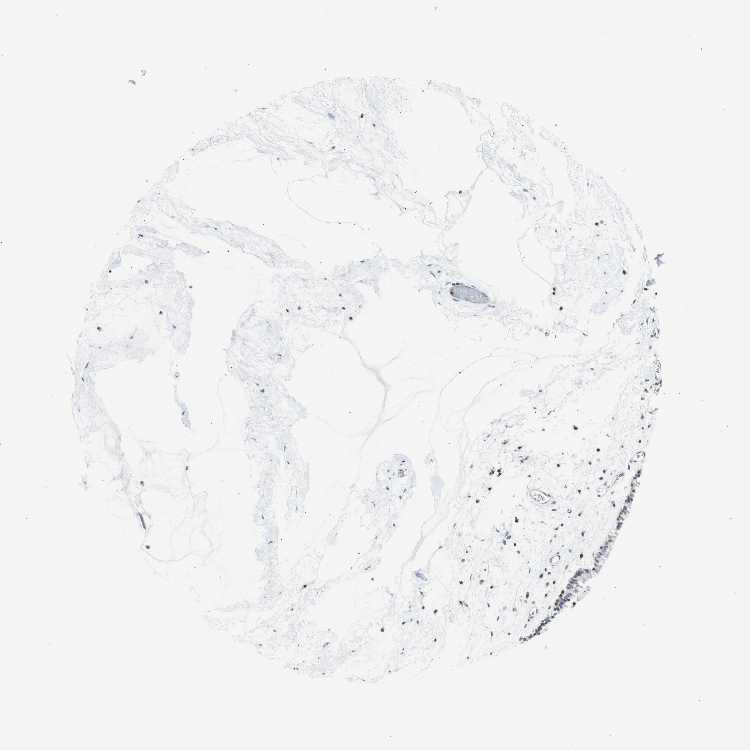

NASOPHARYNX - Antibody stainingi

Antibody staining in the annotated cell types in the current human tissue is reported as not detected, low, medium, or high, based on conventional immunohistochemistry profiling in selected tissues. This score is based on the combination of the staining intensity and fraction of stained cells.

Each image is clickable and will lead to virtual microscopy that enables deeper exploration of all samples and also displays staining intensity scores, fraction scores and subcellular localization as well as patient and tissue information for each sample.

Antibody HPA046833Antibody CAB004545

Respiratory epithelial cells LowNot detected